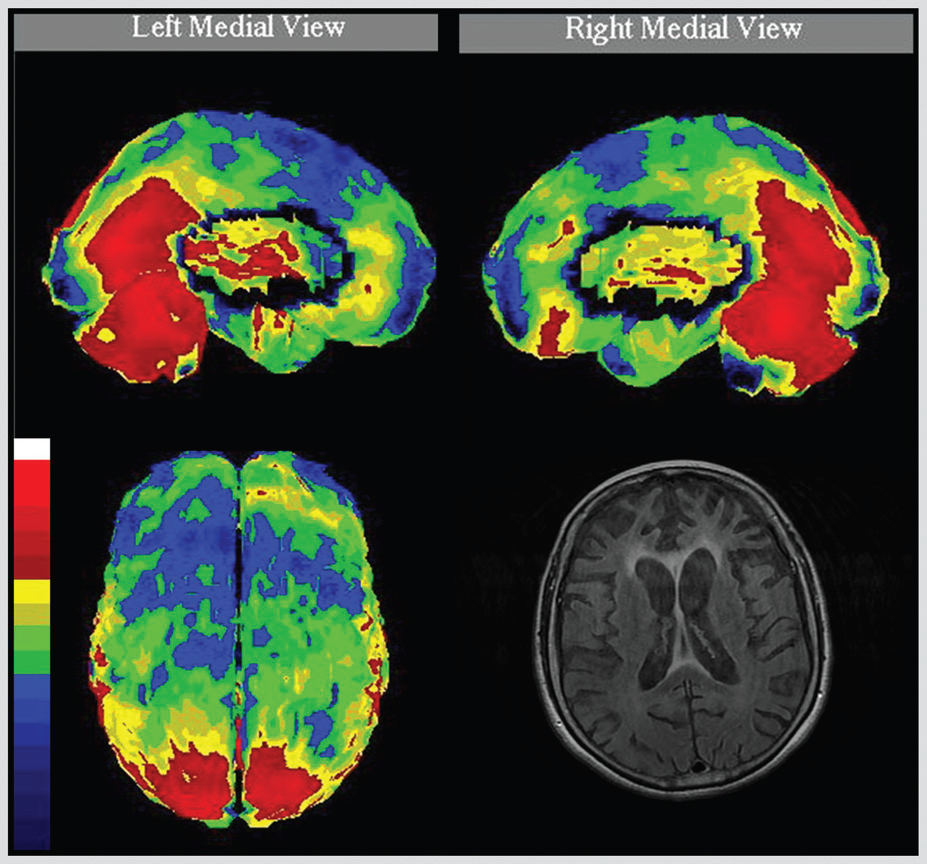

Where are structural or functional abnormalities that can cause an altered state of consiousness?

PARIETAL LOBE:

Describe the characterstics of a deficit in the parietal somatosensory association cortex on the non-dominant side:

OCCIPITAL LOBE:

Describe how lesions in the primary visual cortex affect vision:

Homonymous hemianopia with macular sparing: